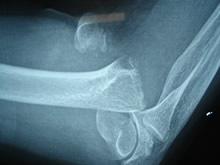

肱骨外髁骨折是常见的儿童肘部骨折之一,约占儿童肘部骨折的6.7%,其发生率仅次于肱骨髁上骨折劢。常见于5-10岁儿童。骨折块常包括外上髁、肱骨小头骨骺部分滑车骨骺及干骺端骨质,属于Salter-Harris骨骺损伤的第Ⅳ型。